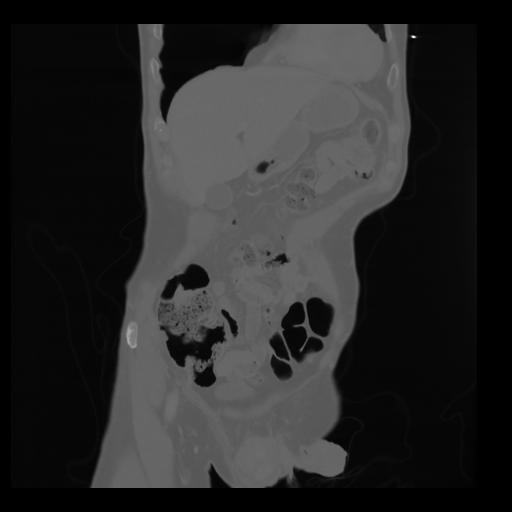

35 CUERPO,CE,Coronal,3.000,CUERPO,Coronal,